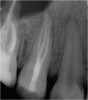

Excellent diagnosis essentially begins with two fundamental components: a doctor willing to listen to the patient’s chief complaint, and proper diagnostic tools. Among the most important tools are a precise periapical radiograph (PA) and bitewing (BW). Although a PA is often enough to provide an accurate portrayal of the patient’s condition, sometimes it alone does not suffice. Figure 1, Figure 2, and Figure 3 demonstrate a case that illustrates this point clearly. Despite two acceptable PAs (Figure 1 and Figure 2), it is difficult to assess the source of the patient’s pain to temperature. However, the BW radiograph Figure 3 provides significantly more clarity than either of the two PAs. The BW depicts localized bone loss (around tooth No. 2), a pulp stone (No. 2), a flat occlusion, numerous calcified canals, multiple restorations in tooth No. 30, and gross decay especially on tooth No. 3, which is the source of the patient’s pain to temperature. In this instance these images depict how much more useful a BW can be than just a conventional PA.

Fig 2. Acceptable PA radiograph.

Figure 2